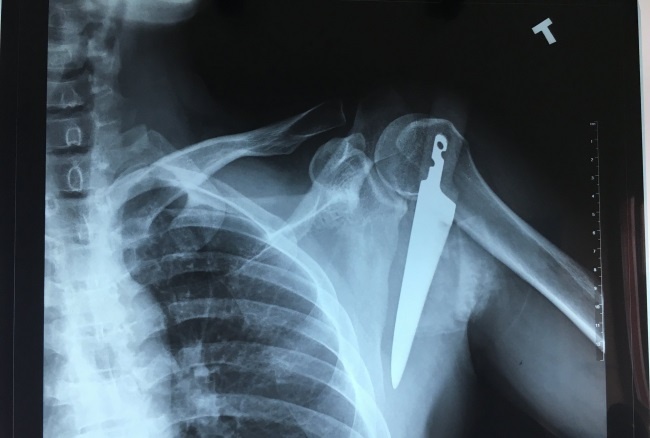

Ngày 8/2, Anh L.T.T (35 tuổi, Uông Bí, Quảng Ninh) nhập viện với một con dao găm sâu vào vai trái ngay 1/3 giữa dưới xương đòn, chảy nhiều máu. Anh T. cho biết khi vào bếp, vô tình vấp ngã và bị dao găm vào vai. Gia đình vội đưa anh đến Bệnh viện Việt nam - Thụy Điển Uông Bí điều trị.

| Con dao được lấy ra dài hơn 20 cm. Ảnh: BVCC |

Theo bác sĩ điều trị, người bệnh nhập viện với một con dao găm ngập cán vào vùng vai trái ngay dưới xương đòn, mất nhiều máu. Vị trí này gần ngay các động mạch lớn và đám rối thần kinh cánh tay. Nếu không được tiến hành phẫu thuật cấp cứu kịp thời, người bệnh sẽ phải đối mặt với nguy cơ như chảy máu nhiều, mất máu, nhiễm trùng, có thể tử vong.

Các bác sĩ đã nhanh chóng tiến hành phẫu thuật cấp cứu lấy con dao ra khỏi vùng vai trái của người bệnh, nối cơ, xử lý vết thương cho người bệnh.

Con dao được lấy ra sắc, nhọn có chiều dài hơn 20 cm. Hiện tại sức khỏe người bệnh ổn định, vết mổ khô và sẽ được xuất viện trong vài ngày tới.